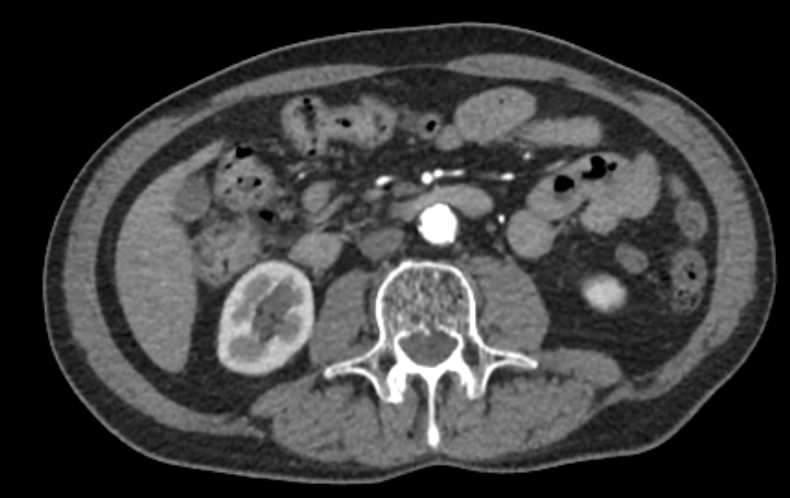

Основные показания для проведения КТ брюшного отдела аорты и артерий нижних конечностей могут включать:

• Аневризмы: оценка и диагностика аневризм брюшной аорты.

• Стенозы и окклюзии: выявление и оценка степени сужения или блокировки артерий.

• Тромбозы: обнаружение тромбов и оценка их размера и локализации.

• Атеросклероз: определение степени и распространенности атеросклеротических изменений.

• Контрастное вещество: введение контрастного вещества может потребовать предварительной оценки функции почек, поэтому необходимо предварительно сдать анализ крови на креатинин.

• Контрастное усиление: контрастное вещество вводится внутривенно. Это помогает улучшить видимость сосудов на изображениях.